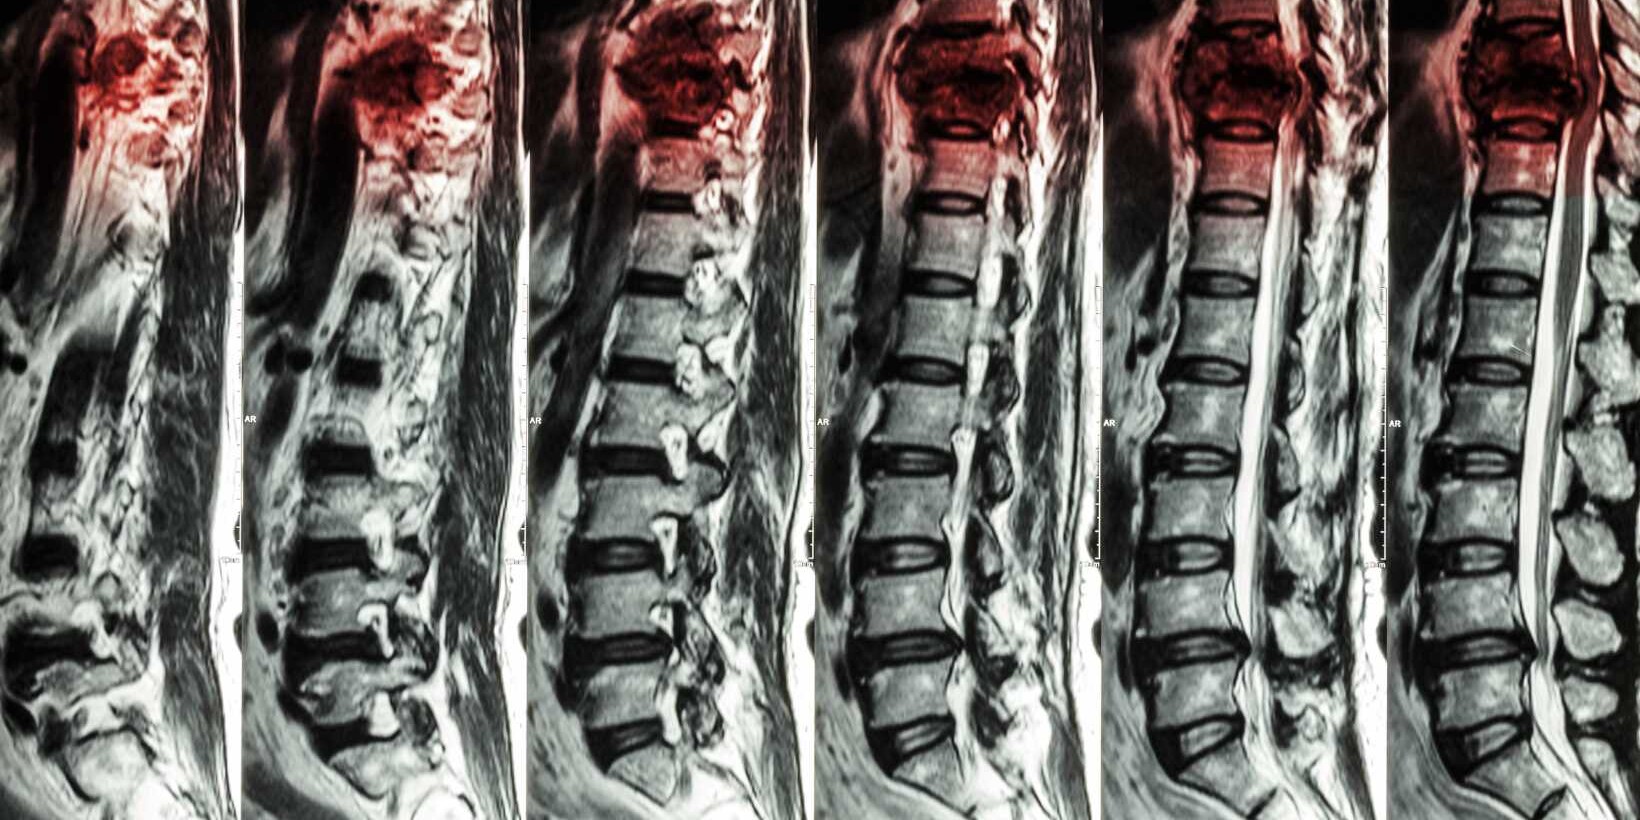

Understanding Compression of the Spinal Cord: Key Facts

Facing compression of the spinal cord can feel overwhelming. But learning the main points helps…

What Is Spinal Stenosis? A Comprehensive Overview

Spinal stenosis happens when nerve roots get pressed in the spine. This often causes pain,…